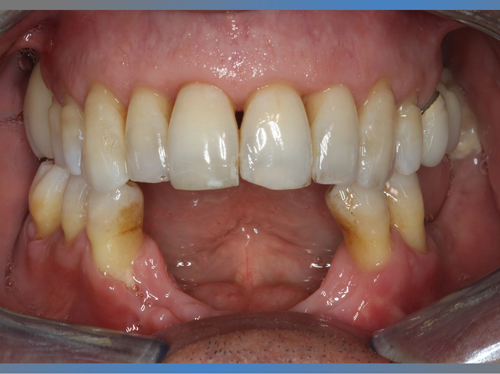

Joaquín vino a la clínica dental en Valencia IDIM a causa del fracaso de unos implantes antiguos.

La infección de estos implantes había causado una pérdida de hueso importante en la zona anterior de su mandíbula.